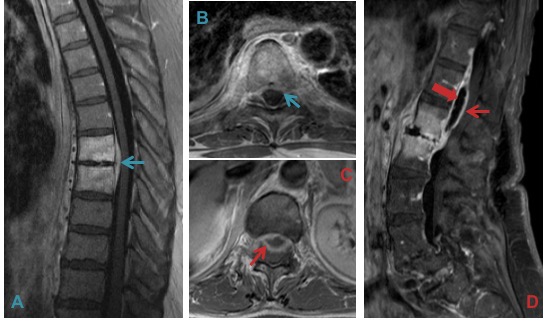

Rare cystic degeneration (A & B) is best identified on fluid-sensitive images (A). Fluid accumulation after disc surgery such as microdiscectomy results in a discal pseudocyst (C & D).